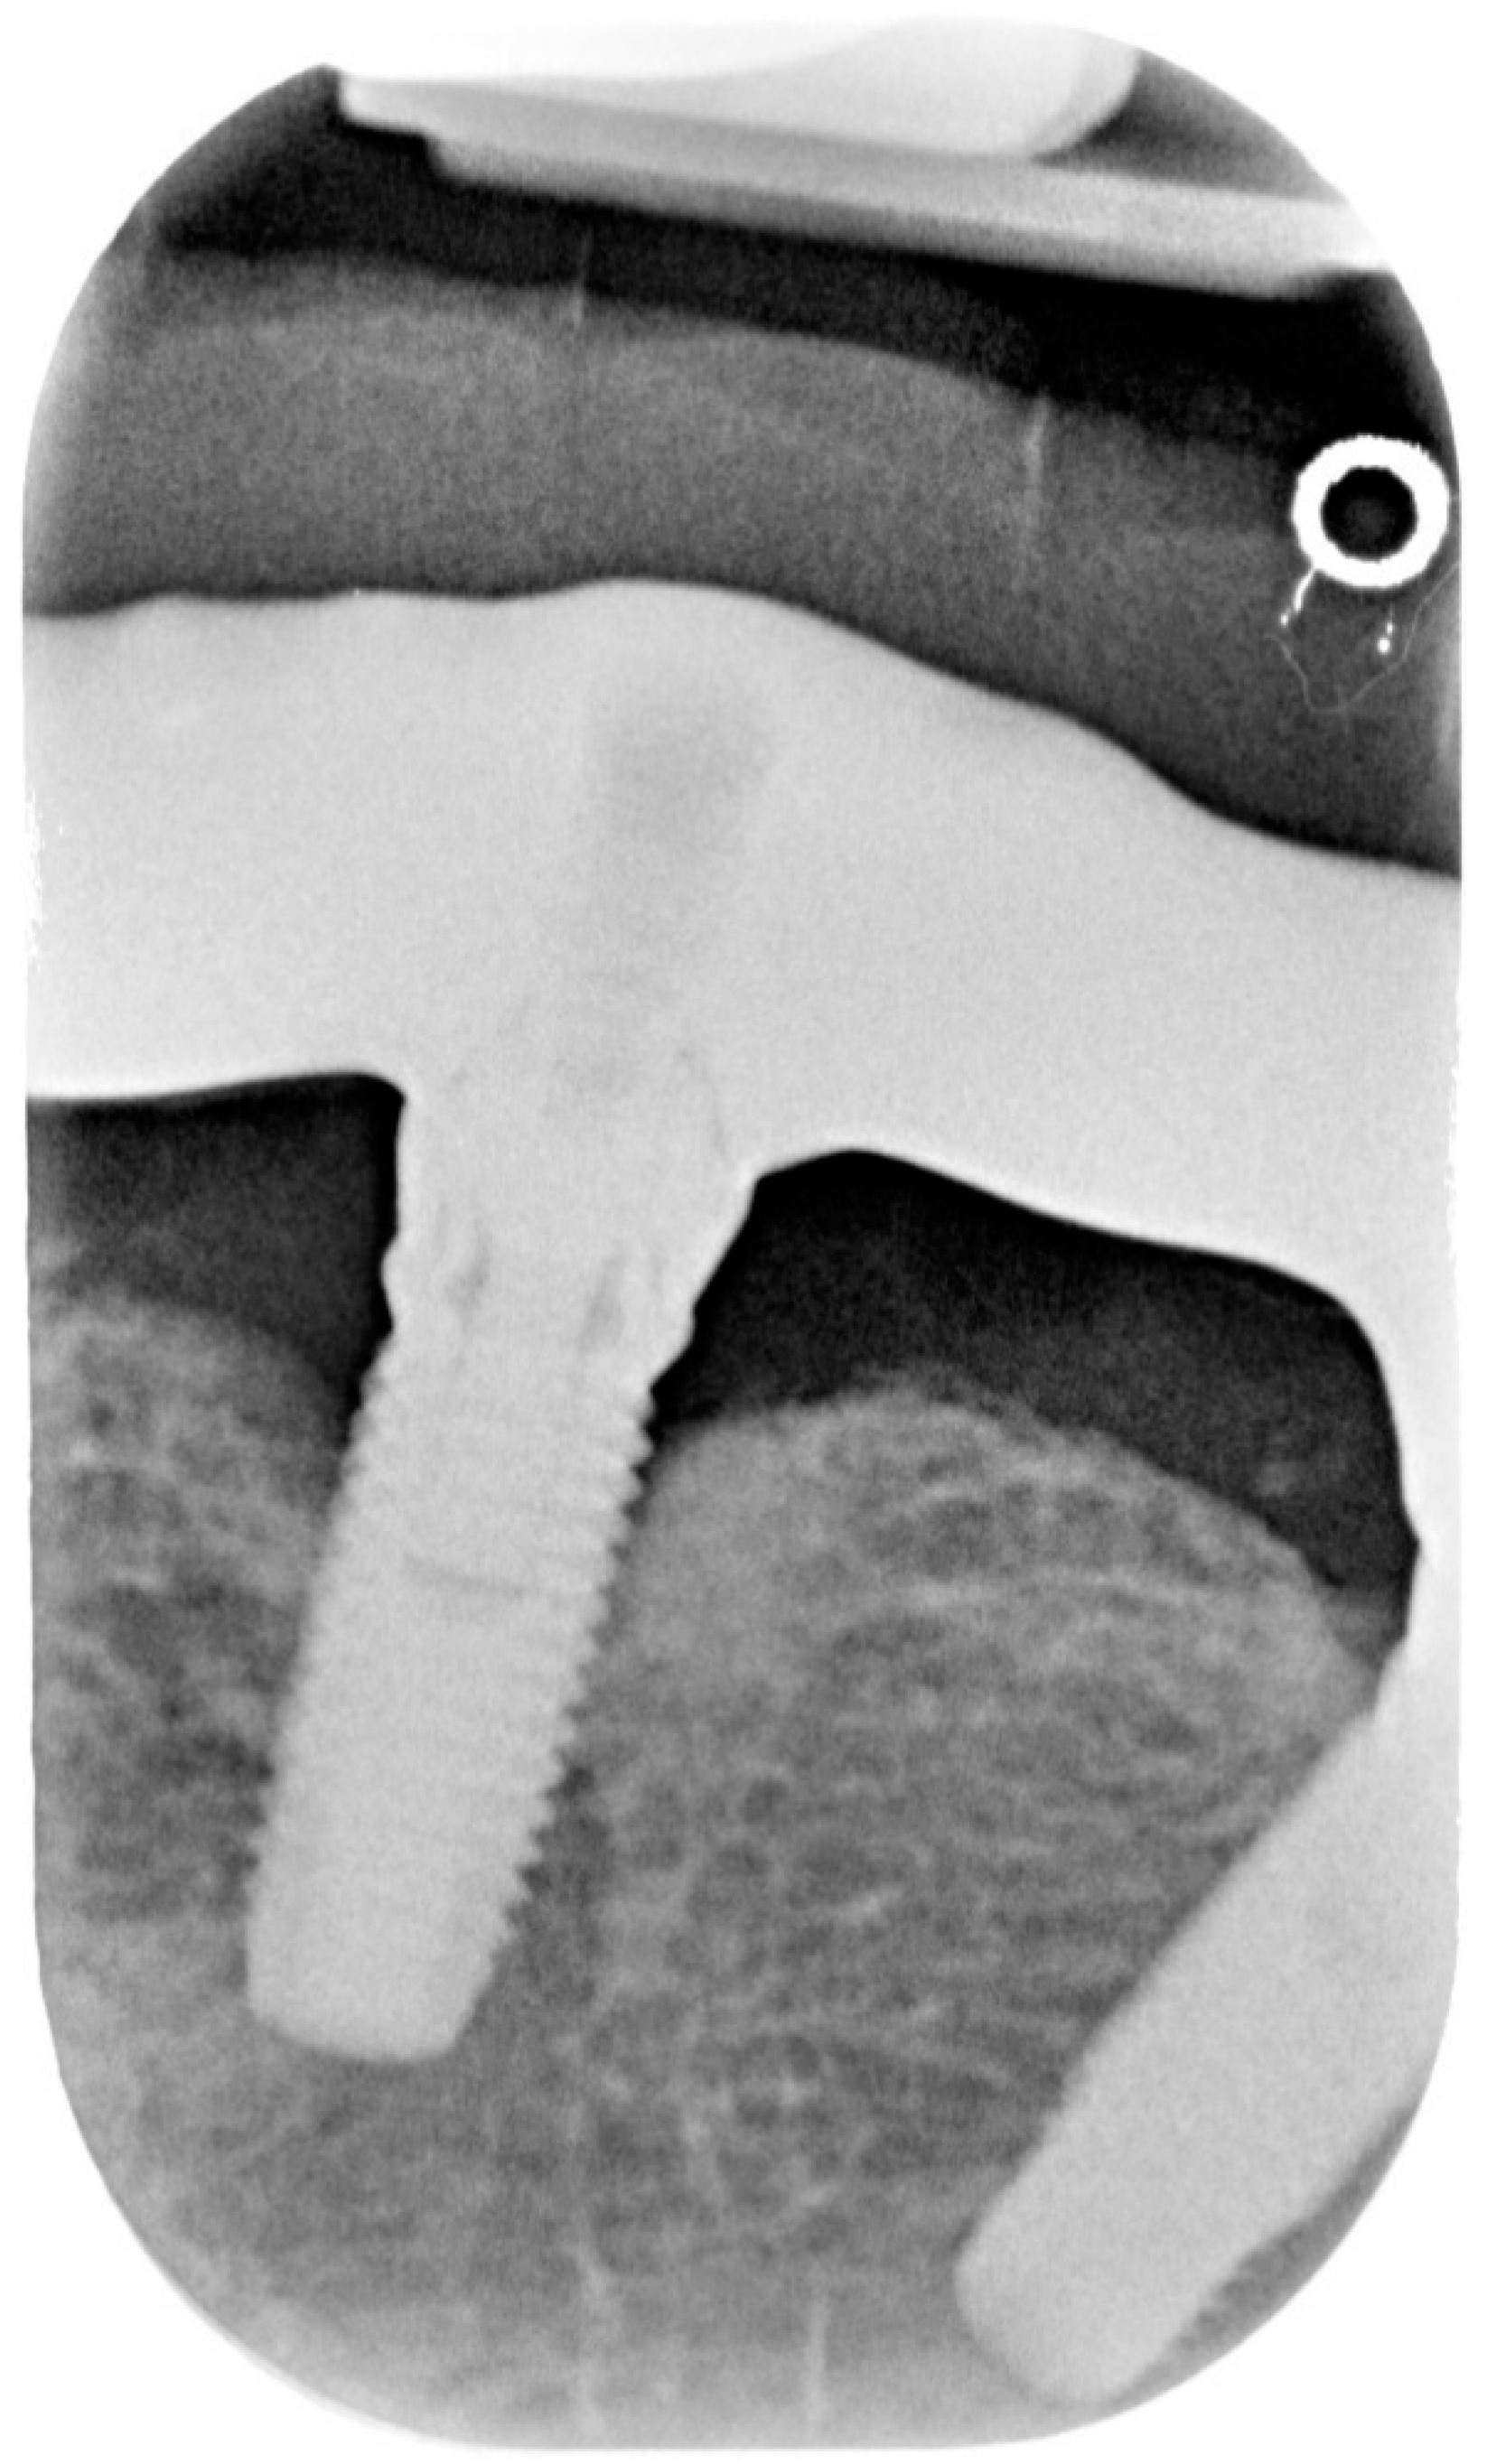

2.1. Case Report 1